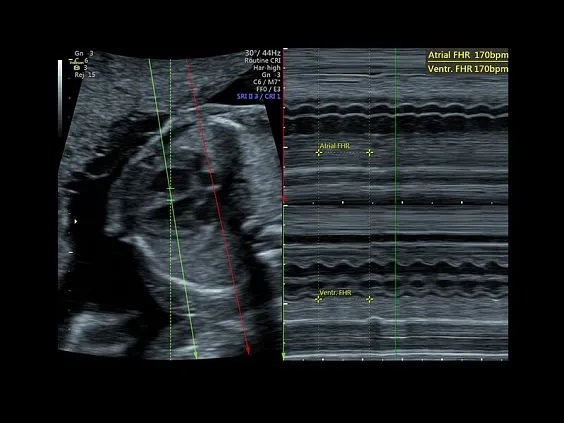

Клинические изображения

Несмотря на демократичную цену, Voluson P8 обеспечивает изображение экспертного уровня, включая поддержку 3D/4D-визуализации, что делает его востребованным в акушерстве и гинекологии. Он построен на платформе Voluson Core Architecture, которая гарантирует высокое качество двухмерной и трёхмерной визуализации, а также стабильную производительность при рутинных исследованиях.

Voluson P8 одинаково уверенно справляется как с задачами в сфере женского здоровья (оценка развития плода, диагностика патологий малого таза), так и при сканировании сердца, сосудов, органов брюшной полости и поверхностных структур. Аппарат поддерживает современные технологии обработки изображения: HD-Flow™, Speckle Reduction Imaging (SRI), CrossXBeam™, что позволяет получить максимально чёткие и информативные данные даже в сложных клинических условиях.

- Эхокардиография плода;

УЗИ аппарат Voluson P8 (серии Performance) создан для решения ежедневных задач. С ним ультразвуковое исследование становится абсолютно простым и доступным методом диагностики, помогающим принимать в акушерской и гинекологической практике важные клинические решения.

Визуализация в режимах 3D/4D позволяет исследовать дополнительные анатомические плоскости, повышая вашу уверенность в диагностике.